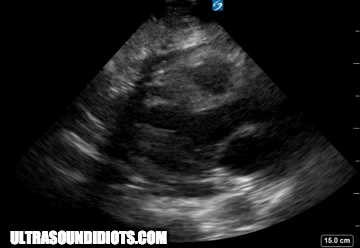

parasternal long axis - standard view